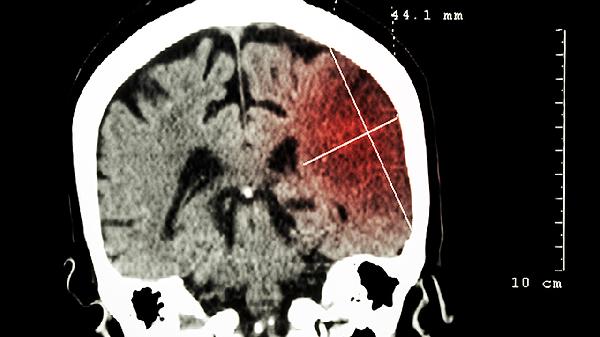

CT检查对脑脓肿的诊断具有较高敏感性,能够清晰显示脓肿的位置、大小以及周围脑组织水肿情况。在脑脓肿早期,CT平扫可表现为边界模糊的低密度灶,增强扫描后脓肿壁呈现环形强化。CT检查的优势在于操作简便、耗时短,适合急诊患者或无法耐受长时间检查的患者。对于存在颅骨伪影或后颅窝病变的患者,CT可能受到一定限制。

MRI检查在脑脓肿诊断中具有更高分辨率和多序列成像优势。T1加权像上脓肿呈低信号,T2加权像呈高信号,增强扫描可见明显环形强化。弥散加权成像能有效区分脑脓肿与其他囊性病变,表现为弥散受限高信号。MRI对脑干、小脑等后颅窝病变显示更清晰,但检查时间较长,且不适用于体内有金属植入物的患者。

脑脓肿患者需在医生指导下根据病情选择合适的影像学检查。CT和MRI均可作为脑脓肿诊断的有效手段,必要时可联合使用以提高诊断准确性。影像学检查结果需结合临床表现及其他实验室检查综合判断,为后续治疗方案的制定提供依据。